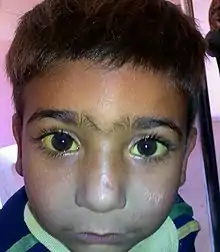

Jaundice, also known as icterus, is a yellowish or greenish pigmentation of the skin and sclera due to high bilirubin levels.[3][6] Jaundice in adults is typically a sign indicating the presence of underlying diseases involving abnormal heme metabolism, liver dysfunction, or biliary-tract obstruction.[7] The prevalence of jaundice in adults is rare, while jaundice in babies is common, with an estimated 80% affected during their first week of life.[8] The most commonly associated symptoms of jaundice are itchiness,[2] pale feces, and dark urine.[4]

The most common signs of jaundice in adults are a yellowish discoloration of the white area of the eye (sclera) and skin[13] with scleral icterus presence indicating a serum bilirubin of at least 3 mg/dl.[14] Other common signs include dark urine (bilirubinuria) and pale (acholia) fatty stool (steatorrhea).[15] Because bilirubin is a skin irritant, jaundice is commonly associated with severe itchiness.[16][17]

Eye conjunctiva has a particularly high affinity for bilirubin deposition due to high elastin content. Slight increases in serum bilirubin can, therefore, be detected early on by observing the yellowing of sclerae. Traditionally referred to as scleral icterus, this term is actually a misnomer, because bilirubin deposition technically occurs in the conjunctival membranes overlying the avascular sclera. Thus, the proper term for the yellowing of "white of the eyes" is conjunctival icterus.[18]